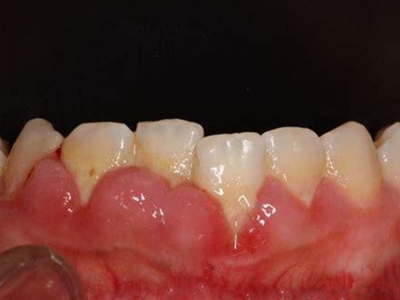

慢性龈炎的病损部位一般局限于游离龈和龈乳头,以前牙区为主,尤其以下前牙区最为显著,患者常因刷牙或咬硬物时牙龈出血而就诊。游离龈和龈乳头颜色变为鲜红或暗红色,病变较重时炎性充血可波及附着龈。龈缘变厚,龈乳头圆钝肥大,可增生呈球状,覆盖牙面。牙龈松软脆弱,缺乏弹性。

龈缘附近牙面上堆积的牙菌斑是引起慢性龈炎的始动因子,其他如牙石、食物嵌塞、不良修复体等均可促使牙菌斑积聚,引发或加重牙龈炎症。